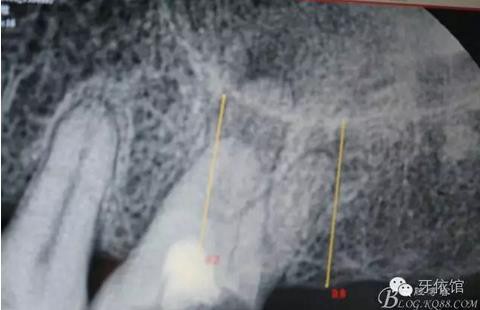

患者女,45歲,右上6于多年前牙髓失活后充填,未作冠,術(shù)前不久,進(jìn)食時(shí)不幸劈裂。檢查發(fā)現(xiàn):右上6充填物脫落,近遠(yuǎn)中向縱劈,x光見(jiàn)根管內(nèi)無(wú)充填物。同時(shí)有右上7、右下7缺失。計(jì)劃:右上6,7,右下7種植修復(fù)。右上6為即可種植,同時(shí)做內(nèi)提。

X光片